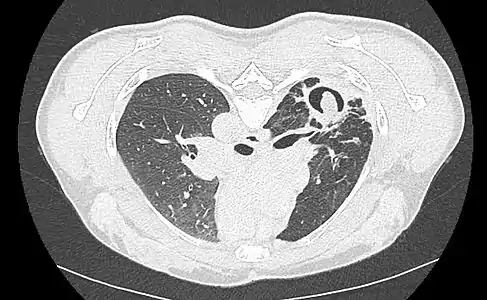

Sur la radiographie pulmonaire, un aspergillome simple apparaît comme un nodule dense, le plus souvent entouré d'un croissant aérique[11]. La radiographie seule ne suffit pas au diagnostic ; un scanner est recommandé[29]. Sur le scanner thoracique, le centre de la cavité est occupé par l'aspergillome[58]. La pseudo-tumeur bouge dans la cavité lorsque le patient change de position (signe de Monod)[58]. Dans l'aspergillome simple, il n'y a pas d'évolution entre les examens et la paroi de la cavité est le plus souvent fine[13]. Un aspergillome complexe[13] présente en revanche l'aspect d'une cavité (ou plusieurs) à parois épaisses, comportant en son centre une truffe aspergillaire. Il existe parfois un début de fibrose pulmonaire[59]. La plèvre adjacente a également un aspect fibrosé, et l'évolution radiologique est lente, mais toujours vers l'aggravation[13]. Un halo en verre dépoli peut également entourer les lésions[45].

Aspect scannographique typique d'un aspergillome développé dans une caverne tuberculeuse.

Le changement de position modifie la position du grelot aspergillaire dans la cavité (signe de Monod).